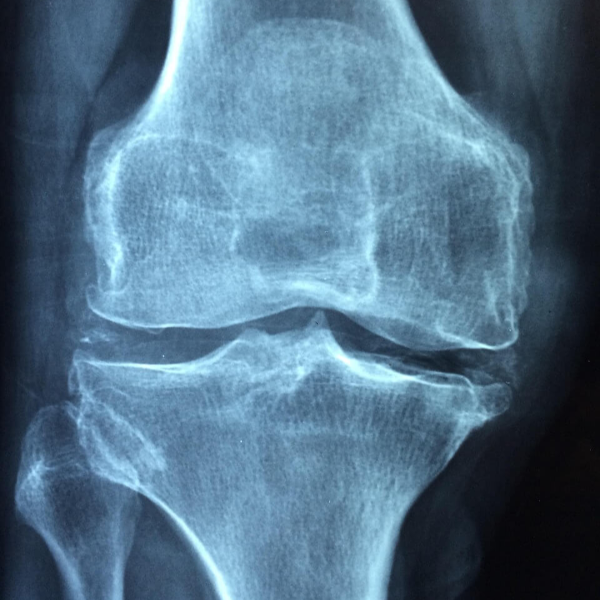

- 연골 손상 또는 관절 염증 소견(비수술적 보조 치료를 원하는 경우)

A. 관절보궁에 들어가는 MSM, 글루코사민, NAG, 보스웰리아 등은 통증 완화나 연골 보존을 돕는 보조적 성분으로 알려져 있습니다. 다만 개인별 차이가 크며 이미 진행된 심한 관절 손상이나 구조적 문제(예: 심한 연골 결손, 골성 변형)가 있는 경우에는 의학적 치료(주사·수술 등)가 필요합니다.